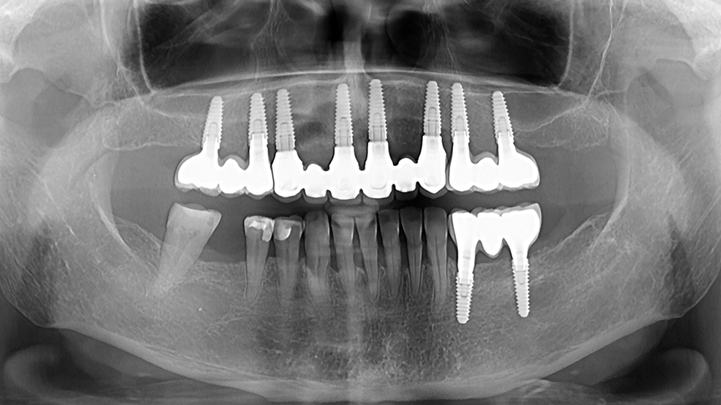

Clinical case: Full-mouth implants for mandibular & maxilla - restored using mixed prostheses

- Courtesy of Dr. Hyun Jun Kim, Korea -

Keywords

AnyRidge, full-mouth implants, mandibular, maxilla, edentulous, full mouth rehabilitation, Octa abutment, long-term clinical case, biological stability, Dr. Hyung Jun Kim

Products:

AnyRidge implant system

“AnyRidge ensures long-term biological stability

& functionality even in

full-mouth rehabilitation case. ”